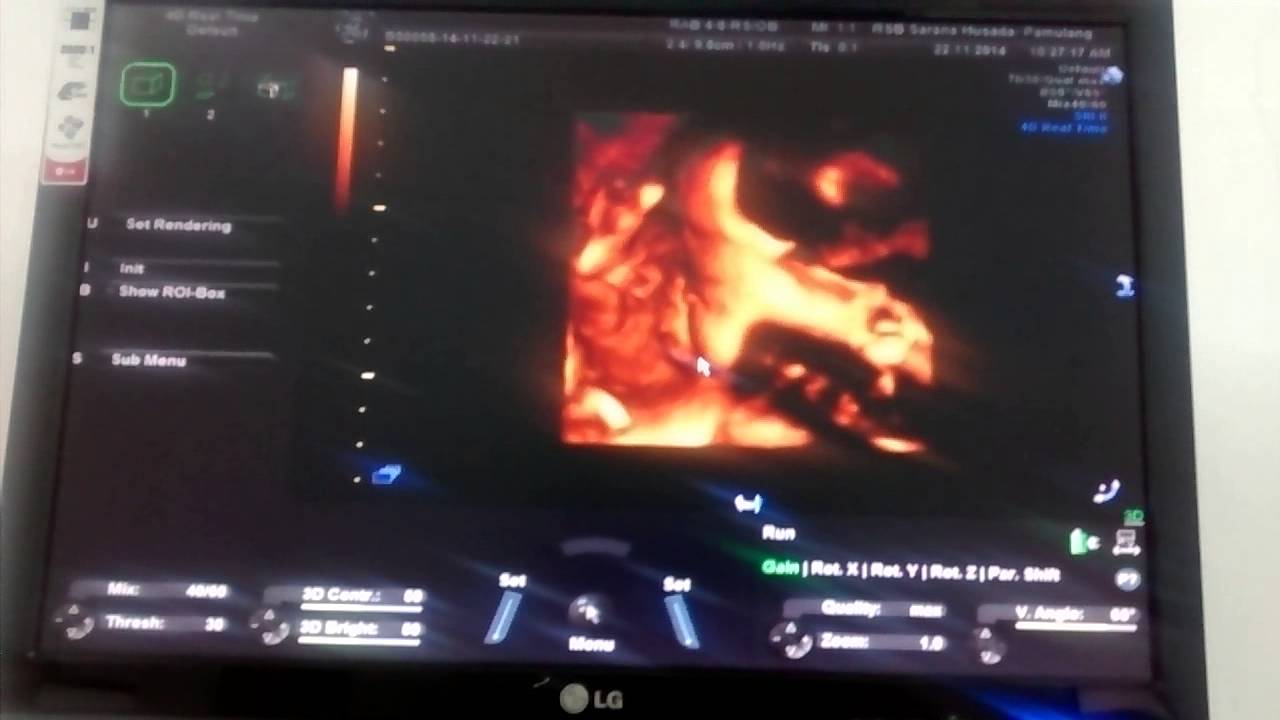

Usg 4d usia kandungan 34-35 minggu - YouTube

Usg 4d usia kandungan 34-35 minggu - YouTube

USG 4D USIA KEHAMILAN 35 MINGGU - JANIN TERSENYUM / FETAL DEVELOPMENT 35 WEEKS THE EMBRYO SMILE - YouTube

USG 4D USIA KEHAMILAN 35 MINGGU - JANIN TERSENYUM / FETAL DEVELOPMENT 35 WEEKS THE EMBRYO SMILE - YouTube

USG USIA KANDUNGAN 35 MINGGU - YouTube

USG USIA KANDUNGAN 35 MINGGU - YouTube